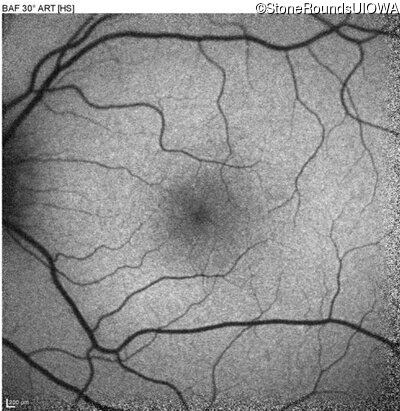

XL Retinoschisis (IIIB1)

XL Retinoschisis (IIIB1)

This 6 year old boy first experienced difficulty reading and seeing the blackboard at age 5.

| XL Retinoschisis | RS1 | Pro192His CCC>CAC | XL |